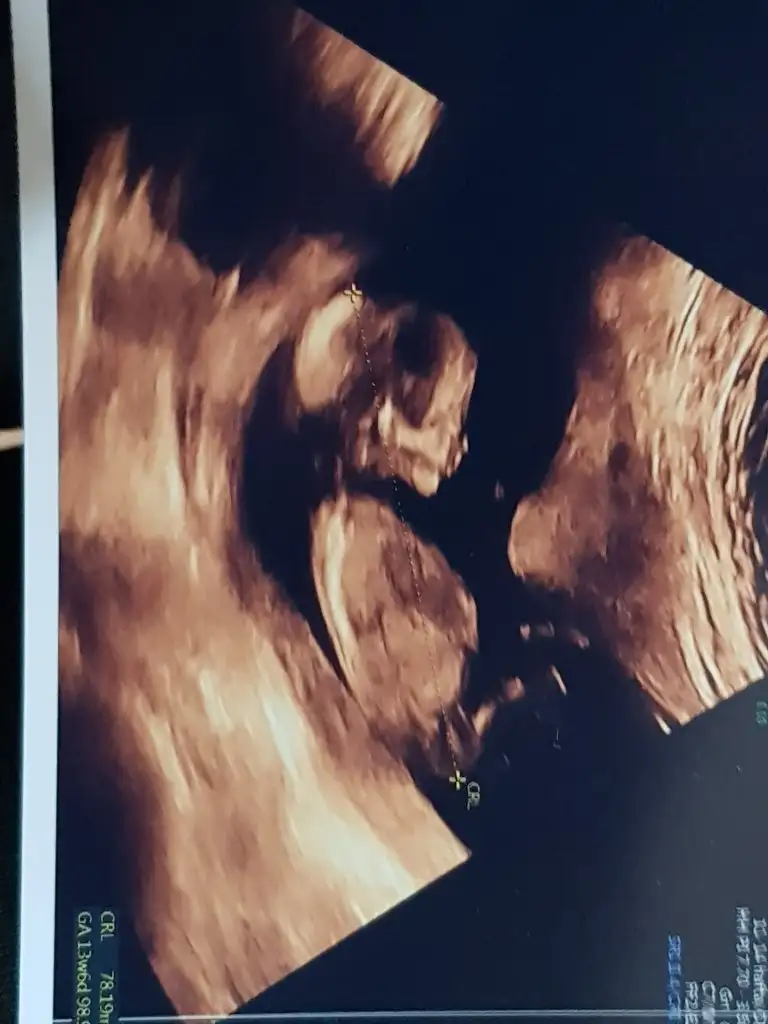

Burda 13+3 canımBana sordunuz bende tahmin ettimnubu yükselirse erkek yönünde 13 haftayida paylaşın

Bunlarda nub gorunmuyorBurda 13+3 canım

Sanki erkek gibi başka USG varsa paylaşın 11 12 13 haftalar olmalıMerhabalar, 13+1 haftalık ultrason görüntüm ekteki gibidir. Cinsiyet konusunda yorumlar mısınız?